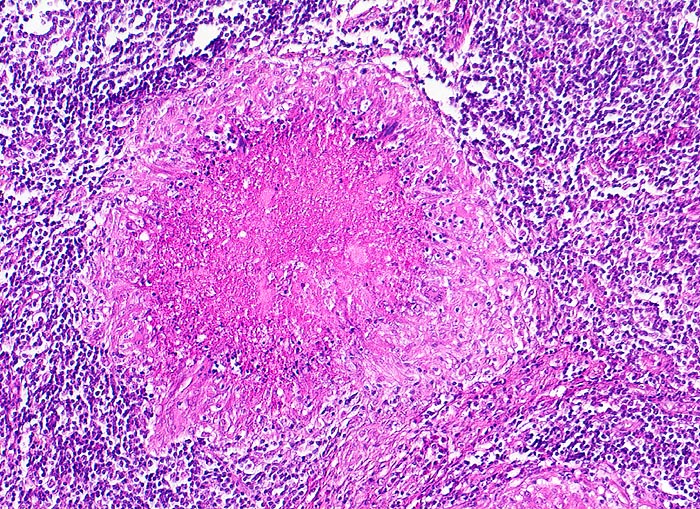

Lymphknotentuberkulose: verkäsendes Granulom

Granulom mit zentraler hypereosinophiler verkäsender Nekrose. Heller Randsaum aus Epitheloidzellen.

Verkäste Granulome treten bei herabgesetzter Resistenz des Organismus auf (exsudative Tuberkulose). Je ausgeprägter die Verkäsung und je geringer die Epitheloidzellreaktion, desto schlechter die Abwehrlage. Im schlimmsten Fall (bei der Tuberculosepsis Landouzy) sind nur noch reaktionslose Nekrosen zu beobachten. Bei guter Abwehrlage fehlt die Verkäsung und es liegen reine Epitheloidzelltuberkel (produktive Tuberkulose) wie bei einer Sarkoidose vor.